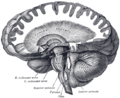

Figure 3: Cerebellum and surrounding regions; sagittal view of one hemisphere. A: Midbrain. B: Pons. C: Medulla. D: Spinal cord. E: Fourth ventricle. F: Arbor vitae. G: Tonsil. H: Anterior lobe. I: Posterior lobe.

The cerebellum is located in the inferior posterior portion of the head (the hindbrain), directly dorsal to the pons, and inferior to the occipital lobe (Figs. 1 and 3). Because of its large number of tiny granule cells, the cerebellum contains more than 50% of all neurons in the brain, but it only takes up 10% of total brain volume. The cerebellum receives nearly 200 million input fibers; in contrast, the optic nerve is composed of a mere one million fibers.